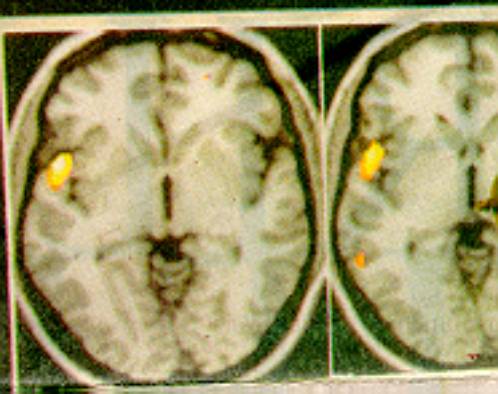

Emozione e gangli della base.

Il sistema dopaminergico esercita un controllo su rinforzi e aspettative

- Strutture nervose come i gangli della base potrebbero custodire gli schemi di emozioni ricorrenti.

La corteccia frontale entra in funzione quando vengono apprese nuove regole ed esperienze, e/o vengono scartate le precedenti, i gangli della base potenziano e richiamano regole ed esperienze precedenti basate su particolari contesti ambientali e storie di rinforzi.